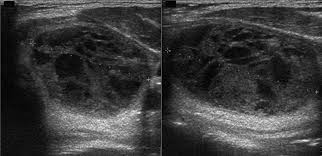

what thyroid pathology is shown here?

multinodular goiter